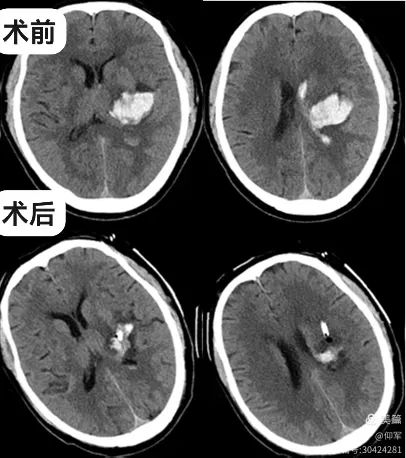

入我院后,查体:嗜睡,言语含糊,右侧肢体肌力1级。复查头颅CT示出血较前增加且破入脑室,约25ml。

术后第三天复查头颅CT可见血肿大部分已引流,引流管位置精准,手术效果良好。